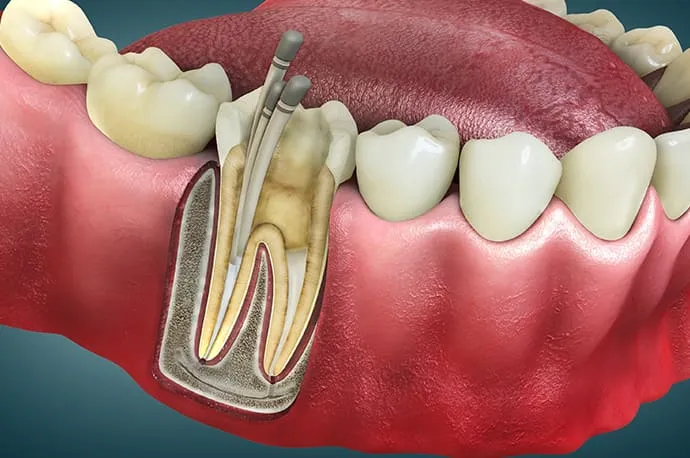

根管治療とは

虫歯が重度に進行すると、虫歯菌が歯の神経まで感染し、歯の内部にある神経を取り除く必要が出てくることがあります。

根管治療とは、文字通り「歯の神経が入っている根の管(根管)」に対して行う治療です。もし根管治療を行わずに放置してしまうと、細菌が歯の根の先にたまり、やがて根の先が化膿してしまいます。その結果、強い痛みが出たり、歯ぐきや頬が腫れたりすることもあります。

根管治療の流れ

STEP 01

虫歯の除去と歯の補強

まずは虫歯を徹底的に取り除きます。虫歯を取り終えた後、治療中に細菌が入り込まないよう、歯の欠けた部分を一時的に補強します(隔壁)。

STEP 02

根管口を探す

歯の内部にある神経の部屋(髄室)へアプローチします。歯や患者さまによって神経の入っている根管の数は異なるため、それぞれの入り口(根管口)を慎重に探し出します。

STEP 03

根管の長さの測定

根管口が見つかったら、ファイルと呼ばれる細い針金のような器具を根の先まで挿入し、根管の正確な長さを測定します。この工程が、治療の精度を左右する重要なポイントになります。

STEP 04

根管の清掃・消毒

測定した長さに合わせて、柔軟性のあるニッケルチタンファイルで根管を最小限に広げます。同時に消毒剤を使用し、根管内部を徹底的に洗浄・消毒していきます。